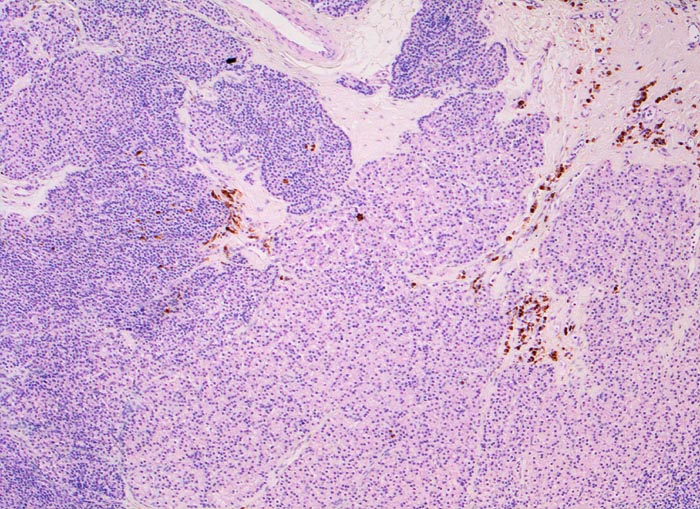

noduläre Nebenschilddrüsenhyperplasie

Das Gewebe ist knotig strukturiert und enthält keine Fettzellen. In den Bindegewebssepten sind braun gefärbte Zellen nachweisbar, die siderinbeladenen Makrophagen entsprechen.

Der Patient leidet an einer chronischen Niereninsuffizienz. Die glomeruläre Filtrationsrate ist auf 25% reduziert. Unter anderem ist eine Hypokalzämie und eine Hyperphosphatämie vorhanden. Die Serumkonzentration des Parathormons ist erhöht. Die Diagnose eines sekundären Hyperparathyreoidismus wird gestellt.